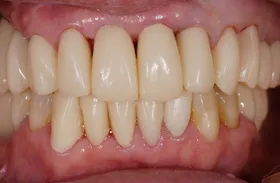

他院で「歯槽膿漏は治らない」と言われ、当院にご来院されました。歯が乱ぐいのため、歯並びもよくしたい、下は歯を既に失っているので噛めるようにもなりたい、またコーラスをされていて人前で口をあけることが多いので、できるだけ見た目を意識した治療をしてほしいとのご要望でした。

■治療(仮歯装着)後